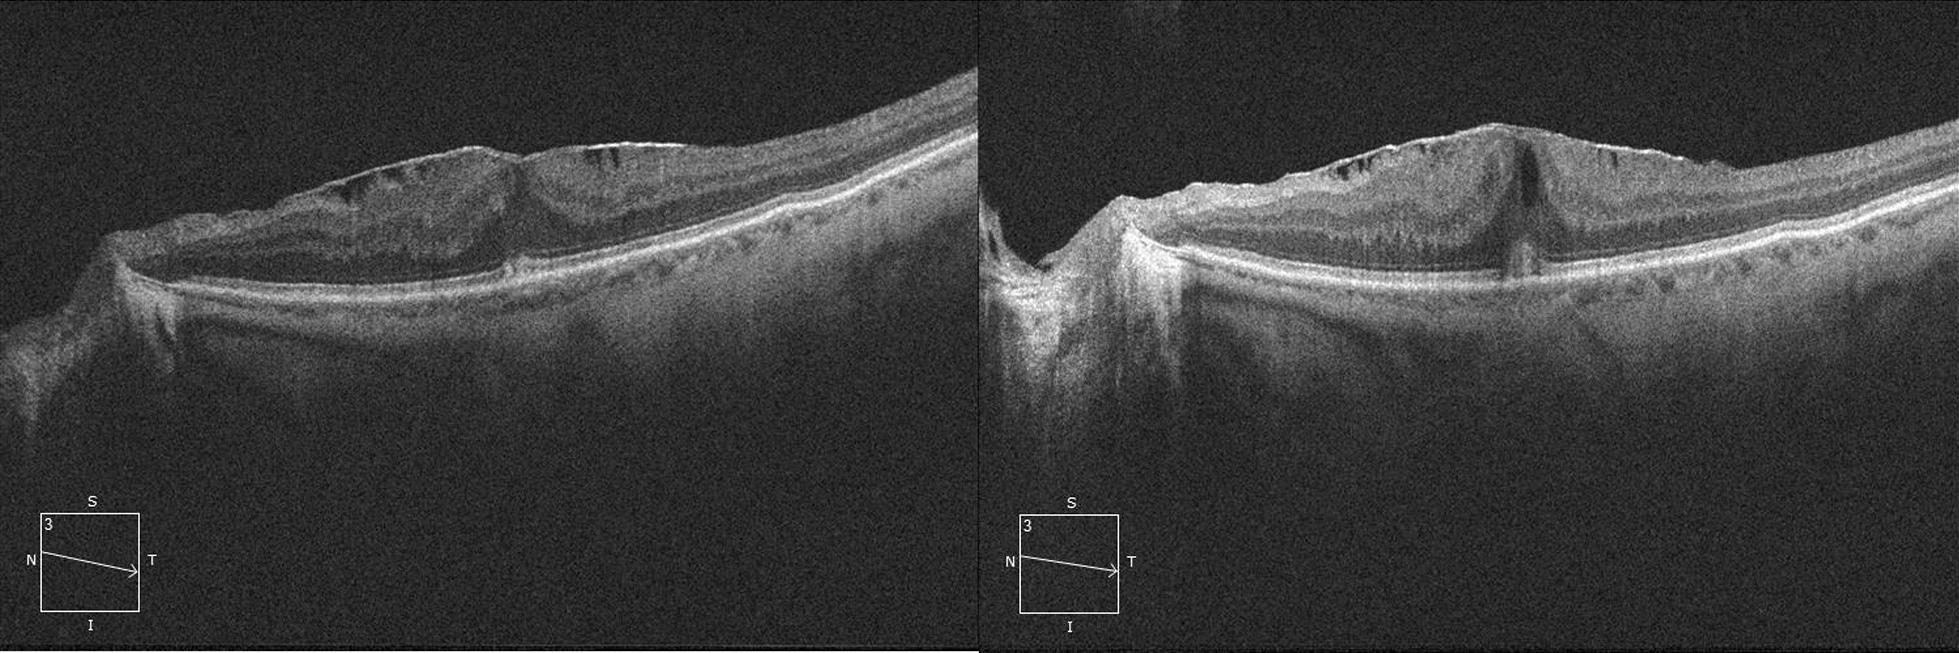

Cataract surgery was not associated with an ERM stage progression at one month follow up, but caused retinal inflammation that resulted in a significant increase in central macular thickness (CMT), macular volume (MV), central macular edema (CME), IS/OS disruption (IS/OS) and neurosensory detachment (NSD). However, there was no significant change in Best corrected visual acuity (BCVA).

白内障手术在术后1个月随访时与ERM分期进展无关,但引起视网膜炎症,导致中心黄斑厚度(CMT)、黄斑体积(MV)、中心黄斑水肿(CME)、IS/OS中断(IS/OS)和神经感觉脱离(NSD)显著增加。然而,最佳矫正视力(BCVA)无显著变化。